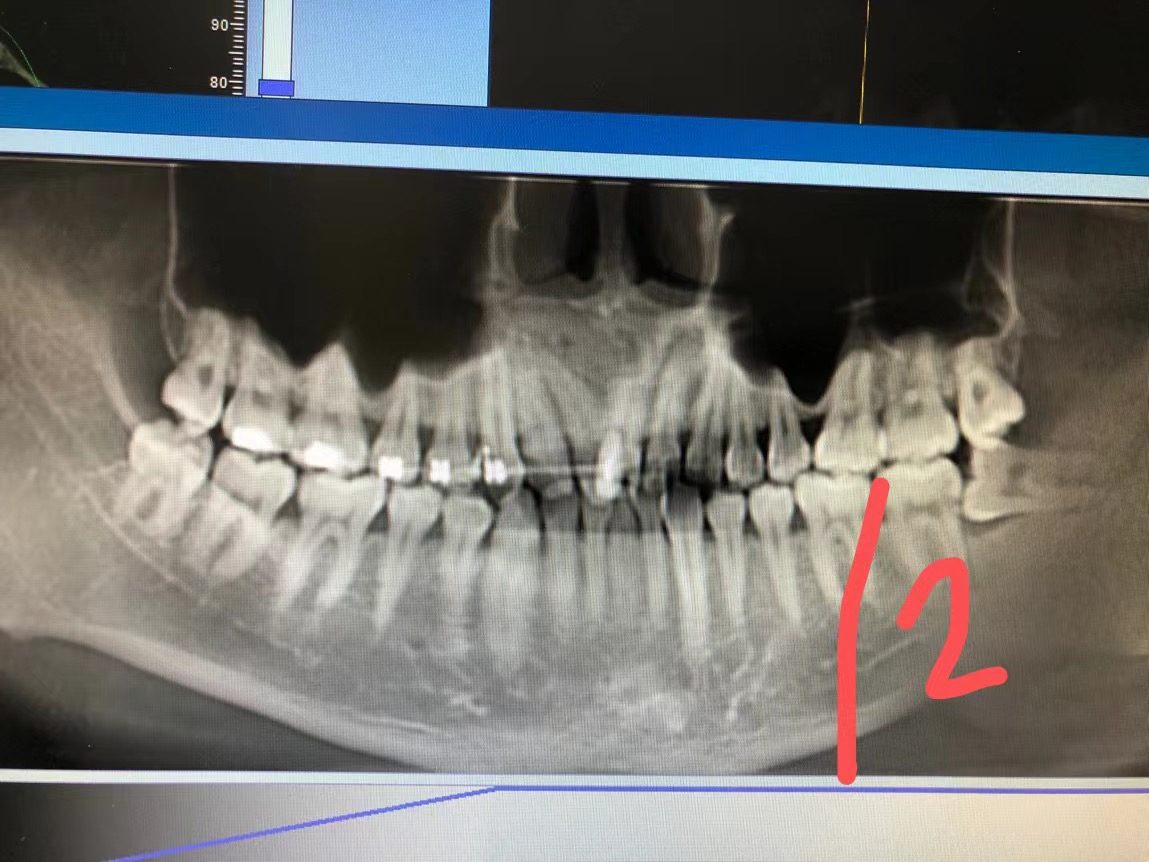

4、移位埋伏牙:移位埋伏牙位於(yu) 門牙根間,導致小朋友上門牙間隙過寬。

處理:這種情況需要拍片檢查,如果檢查出是牙瘤、埋伏移位牙或多生牙的情況,要及時進行手術治療。